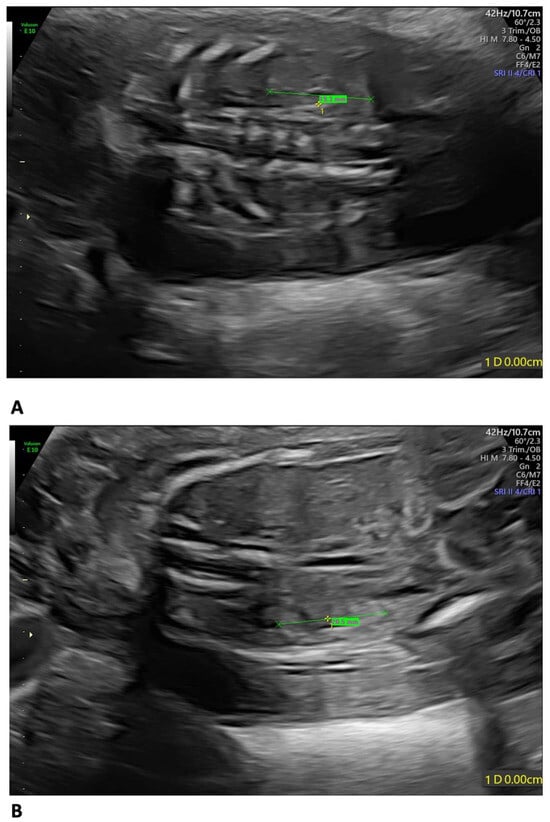

A 35-year-old mother, gravida 2, para 1, regularly attended the scheduled US scans for the first trimester. At 13 weeks of gestation (wg), the US showed no anomalies, and the nuchal translucency (NT) was of 2.12 mm. The Harmony™ non-invasive prenatal test (NIPT) showed a low risk for trisomies 21, 18, and 13. The patient presented at 21 weeks + 3 days for the planned morphological scan of the second trimester. The US showed oligo/anhydramnios, IUGR (fetal measurements below the 1st centile), a velum interpositum cyst, and mild pericardial effusion. The longitudinal diameter of both kidneys was within the normal centile for the gestational age, the left measuring 19.3 mm and the right, 20.5 mm, respectively (Figure 1) [12].

Figure 1.

Fetal US at 21 weeks + 3 days: both kidneys presented a longitudinal diameter within the normal centile for the gestational age, measuring 19.3 mm on the left (A) and 20.5 mm on the right (B).

In our case, the US findings, at 21 weeks + 3 days, included IUGR, oligo/anhydramnios, velum interpositum cyst, and mild pericardial effusion. Despite oligo/anhydramnios, both kidneys were not hypoplastic, measuring in longitudinal diameter 19.3 mm on the left, and 20.5 mm on the right, respectively [12].